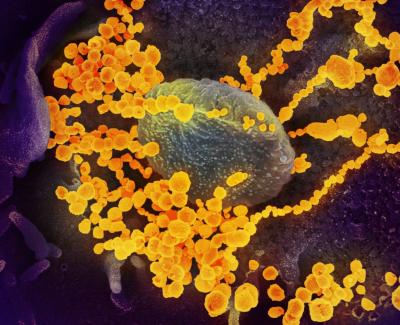

कोरोना व्हायरसमुळे जगभरात भीतीचं वातावरण तयार झालं आहे. कारण कोरोनामुळे मृत्यू होत असलेल्यांची संख्या दिवसेंदिवस वाढत चालली आहे. कोरोनाचं संक्रमण झाल्यानंतर शरीरातील पेशींवर कसा परिणाम होतो. याबाबत आम्ही सांगणार आहोत.

कोरोना व्हायरसच्या संक्रमणामुळे शरीरातील श्वसनप्रणाली निष्क्रीय होत असते. त्यासोबत इतर अंतर्गत अवयवांवर कसा परिणाम होतो. याबाबत द लँसेट यात एक रिसर्च प्रकाशित करण्यात आला आहे.

यात रिसर्चकर्त्यांनी असा दावा केला आहे की कोरोना व्हायरस शरीरातील रक्तवाहिन्यांना आणि रक्ताच्या पेशींना पूर्णपणे खराब करून अवयवांवर परिणाम करत असतो. फुप्फुसांनंतर रक्तवाहिन्यावर कोरोना व्हायरस अटॅक करतो.

या व्हायरसचं संक्रमण निमोनियापेक्षा जास्त घातक आहे. कारण हा व्हायरस पेशीचे सुरक्षा कवच असलेल्या एंडोथिलियम या आवरणापर्यंत जाऊन अटॅक करू शकतो. त्यामुळे रोगप्रतिकराकशक्ती कमी होते.

आरोग्यतज्ञ रुचित्जका यांनी सांगितले की मी आत्तापर्यंत अशा तीन केसेस पाहिल्या आहेत. ज्यात कोरोना रुग्णांच्या रक्तवाहिन्या या व्हायरसने संपूर्ण भरलेल्या होत्या. त्यामुळे शरीरातील अवयवांवर नकारात्मक परिणाम दिसून येत होता.